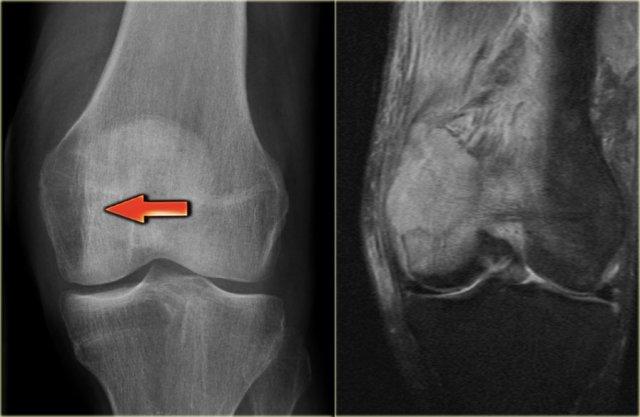

GCT of the radius with ill-defined margins on the left and a GCT in the tibia with well-defined margins

Bên trái là u tế bào khổng lồ ở đầu xa xương quay với bờ không rõ ràng, phá hủy tấm xương dưới sụn và xâm lấn vào phần mềm.

Bên phải là u tế bào khổng lồ ở đầu gần xương chày với bờ tương đối rõ hơn và vỏ xương còn liên tục.

Bên trái là hình ảnh của bệnh nhân 60 tuổi có tiền sử ác tính đã biết.

Có một tổn thương ở đầu xa xương đùi, mà bạn có thể dễ dàng bỏ qua và nghĩ rằng đó là loãng xương khu trú.

Tổn thương biểu hiện là một khối tiêu xương lớn, bờ không rõ, lan rộng vào vùng đầu xương và gần như tiếp giáp với bề mặt khớp.

Ở bệnh nhân trong độ tuổi 20-40, u tế bào khổng lồ (GCT) có thể là một chẩn đoán.

Kết quả cho thấy đây là tổn thương di căn.